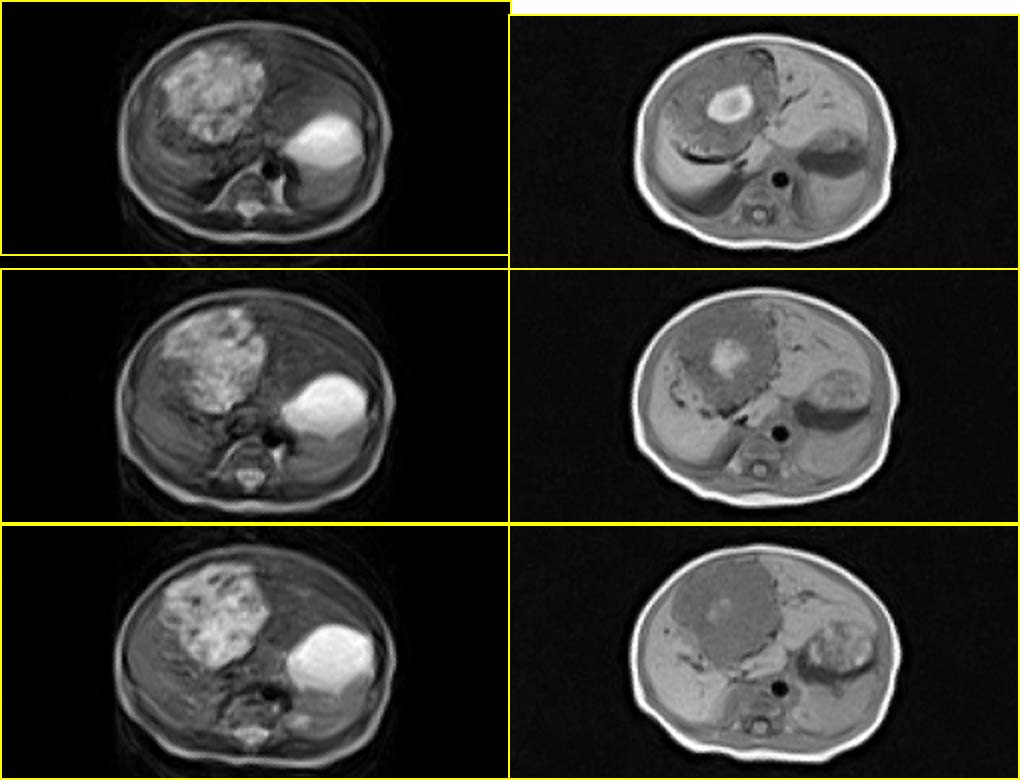

患者男性,3天.

因生育前b超发现肝脏占位,怀疑血管瘤而行mr检查.

血管内皮瘤,建议补充临床资料,如血常规,尤其血小板情况,有无充血性心衰,主要与肝母鉴别.

考虑肝母